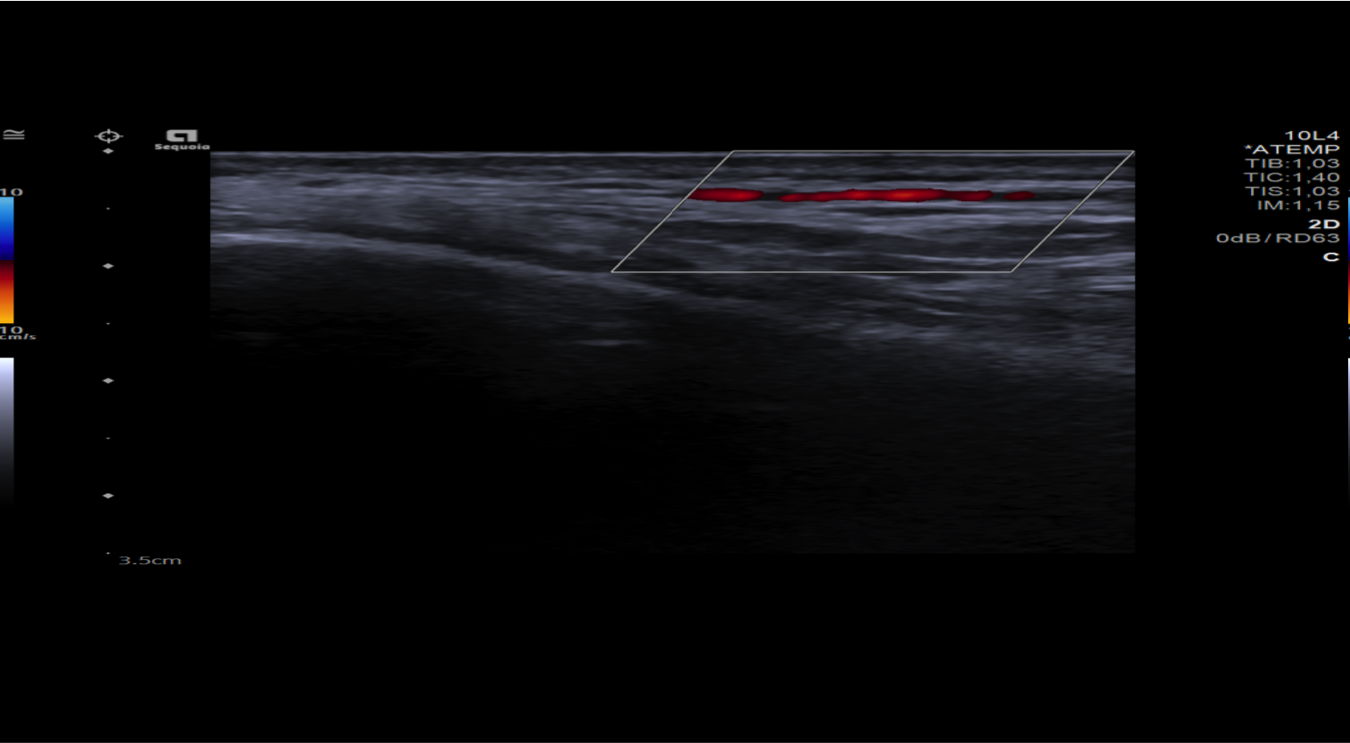

Realizamos una ecografía centrada en la zona temporal derecha del paciente.

Hallazgos ecográficos

Observamos engrosamiento parietal de arteria temporal iderecha con halo hipoecoico periférico, disminución de su calibre y cambios inflamatorios asociados.

Ante la sospecha clínica de arteritis de la temporal decidimos realizar la ecografía en nuestro Centro de Salud.

El paciente ingresó a cargo de Neurología donde solicitaron ecografía modo Doppler de ambas arterias temporales y RMN cerebral. Además, fue valorado por Oftalmología.

En conclusión, ante un paciente de edad avanzada y síntomas que hagan sospechar la presencia de una arteritis de la temporal debe considerarse la realización de una ecografía modo Doppler para su diagnóstico y así evitar el retraso del diagnóstico definitivo mediante biopsia.